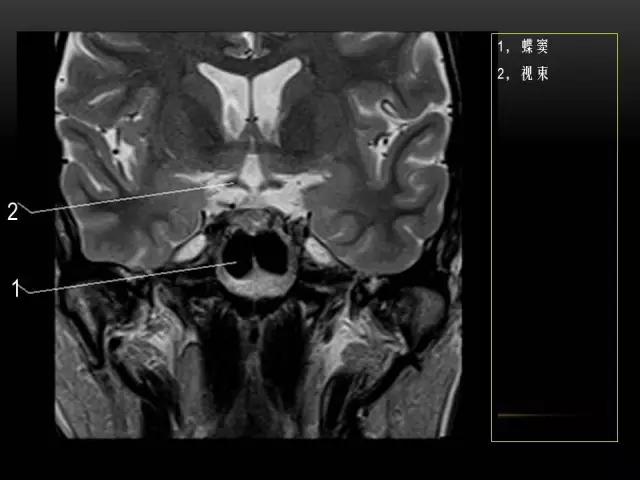

下文是在MRI下眼部及鼻窦的冠状位解剖图谱。